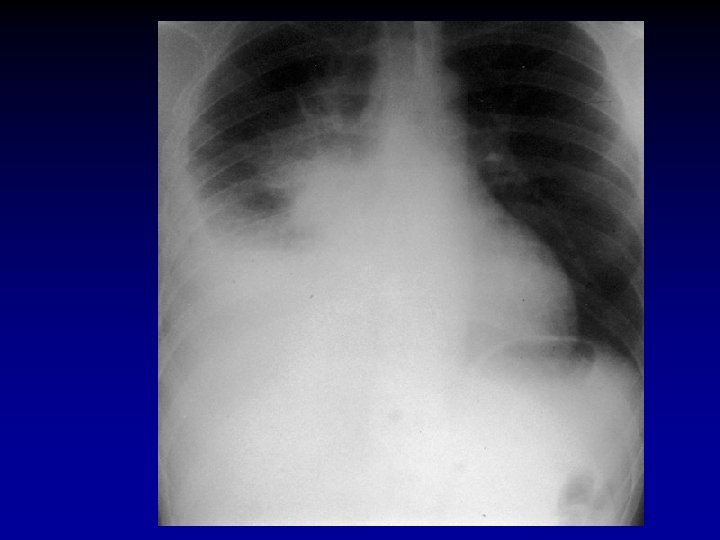

Akciğer Grafisi • Posteroanterior grafi Pnömoninin • Yerini • Komplikasyonlarını • Pnömoniyi taklit eden durumları saptar.

Akciğer Filmi • Pnömoni düşünülen her hastada PA akciğer filmi çekilmelidir • Radyolojik görünümle etyolojik tanıya varmak mümkün değildir • Antibiyotik tedavisine yanıt alınıyorsa bir kontrol filmi yeterlidir • Bazı pnömonili olgularda akciğer filmi normal görünümde olabilir (Pnömoninin ilk 24 saatinde, dehidratasyon, yaşlı, pnömosistis karini, ciddi nötropenik hastalarda)

Akciğer Grafisi • Pnömokok, Klebsiella • Lober tutulum • S. aureus, P. aeruginosa • Bronkopnömonik görünüm • S. aureus • Legionella • Pnömatosel, yeri değişen nodüler infiltrasyonlar, apse • Zaman içinde değişebilir veya baştan itibaren lober